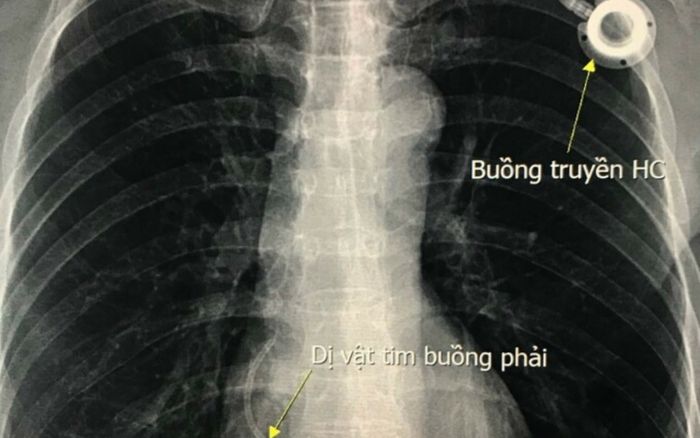

Mới đây, Bệnh viện Hữu nghị Việt Đức tiếp nhận trường hợp người bệnh là phụ nữ 54 tuổi ở Hòa Bình, phát hiện ung thư vú năm 2015, đã phẫu thuật và đặt buồng truyền hóa chất để điều trị hóa chất.